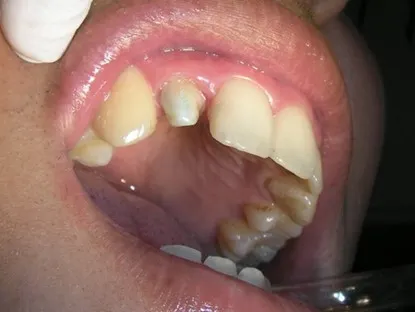

<<三年又三個月前 為陳先生裝#12 Cap-Lock>>

修形、排齦後取模、比色,有蛀牙同時幫他用樹脂填補